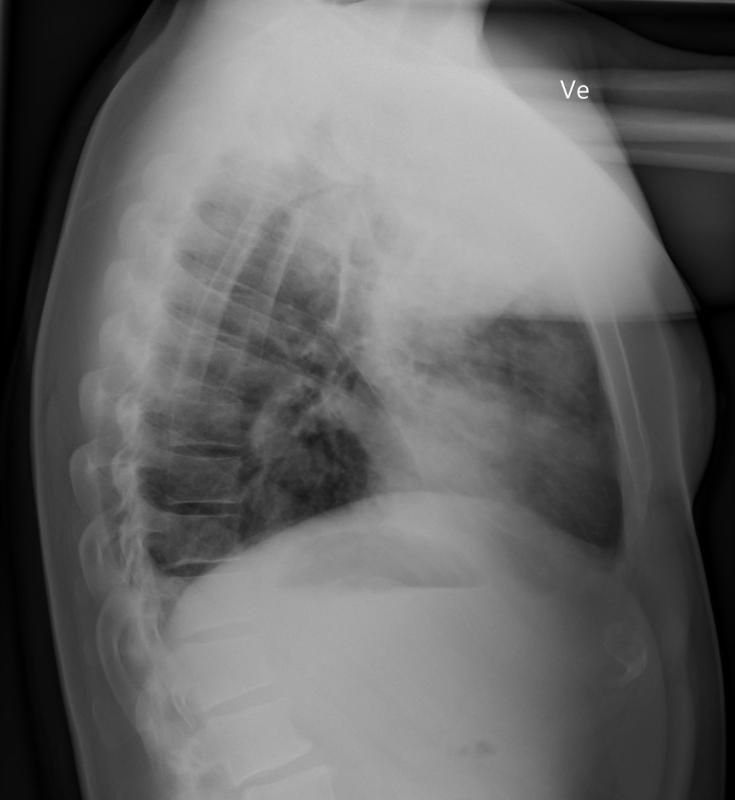

第 2 天复查胸部 X 光检查显示左肺和右上叶有明显进展的实变浸润,进一步支持弥漫性肺泡损伤和微出血的诊断,并怀疑存在 ARDS。

cf9b4ca9e7c128d63b01523251d5c277.jpg